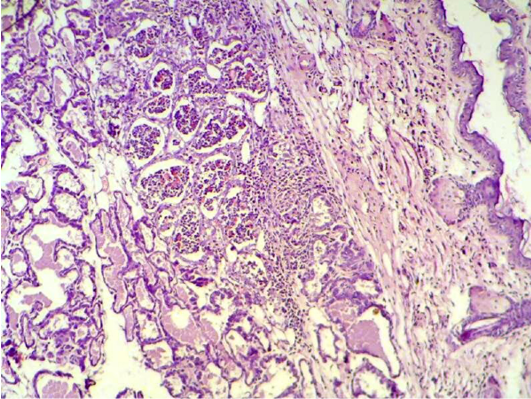

Mammary gland section shows sever destruction of mammary gland with abundant of inflammatory cells infiltration (H&E 200 X)